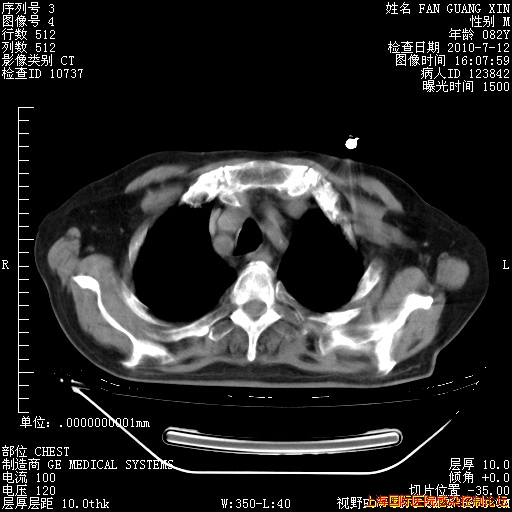

今天复查CT

今天CT

整整相隔30天的肺部CT好像有所好转啊。甲强龙减量第3天,需要观察体温。